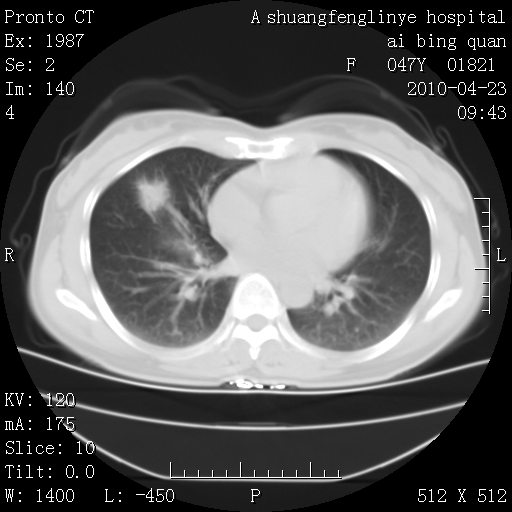

标题: CT25944:胸痛、气短、前几日高烧!肺Ca?请会诊! [打印本页]

标题: CT25944:胸痛、气短、前几日高烧!肺Ca?请会诊!

双肺多发结节,考虑转移瘤,肺癌肺转移不除外

周围型肺癌并肺转移

双肺多发结节,部分密度较高,最大结节边缘光滑。临床有“胸痛、气短、前几日高烧”病史。首选考虑:右肺感染性病变!建议积极消炎后复查!